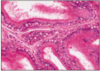

PROSTATIC URETHRA

- urethra longer in males

- prostatic

- membranous

- bulbous

- pendulous

- urothelium (pseudo-stratified columnar) except at distal end

- mucus glands along length

- distal urethra = stratified squamous (male and female)

- both sexes = striated (voluntary) muscle sphincter from muscles of pelvic diaphragm around membranous part

- under prostatic urothelium = dense fibrous connective tissue to prevent distension

inset = U-shaped prostatic urethra